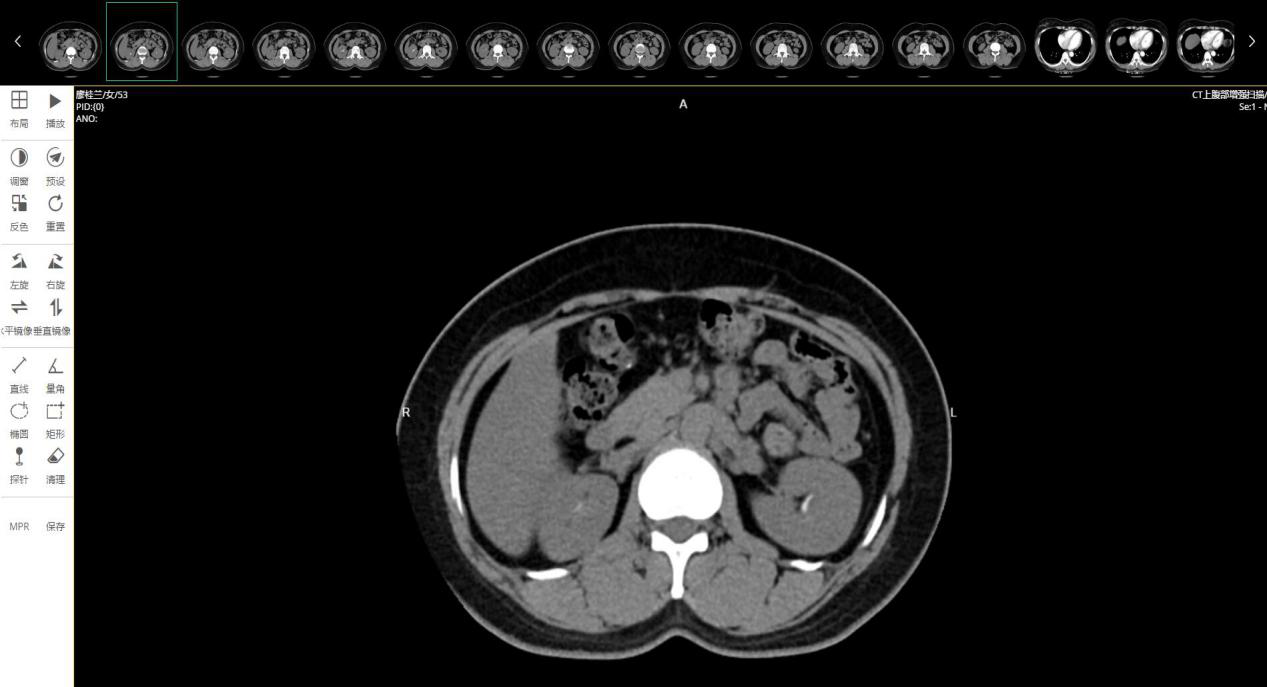

远程影像诊断采用先进的B/S架构,基于Web浏览器技术,无需下载任何插件,PC、iPad、手机在线操作,实现随时随地调阅医学影像。

3、支持所有DICOM标准设备图像

平台支持所有的标准DICOM设备图像,如计算机断层扫描、核磁共振成像、数字X射线成像、超声等。